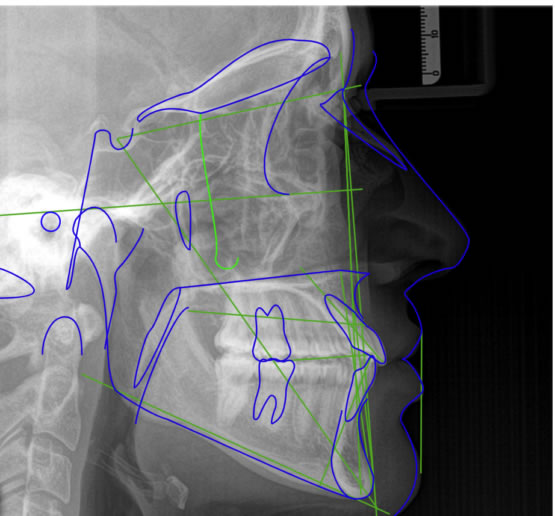

Consiste em um conjunto de exames (radiografias, fotografias intra e extra-bucais, modelos em gesso das arcadas dentárias, análises cefalométricas computadorizadas) cuja finalidade é proporcionar uma visão abrangente do paciente, permitindo que o profissional analise e o auxilie no seu plano de tratamento. Todos esses exames estão contidos em uma pasta e uma caixa específica para colocação dos modelos ortodônticos.

Panorâmica, telerradiografia lateral cefalométrica, 08 fotos intra e extra-orais, modelos de estudo, traçados cefalométricos computadorizados, laudos radiográficos, fichas clinicas, caixa para modelos, pasta de plástico + Série completa.

Panorâmica, telerradiografia lateral cefalométrica, 08 fotos intra e extra-orais, modelos de estudo, traçados cefalométricos computadorizados, laudos radiográficos, fichas clinicas, caixa para modelos, pasta de plástico.

Panorâmica, telerradiografia lateral cefalométrica, 06 fotos intra e extra-orais, modelos de estudo, traçados cefalométricos computadorizados, laudos radiográficos, fichas clinicas, caixa para modelos, pasta de plástico.

Panorâmica, telerradiografia lateral cefalométrica, 08 fotos intra e extra-orais, traçados cefalométricos computadorizados, laudos radiográficos.